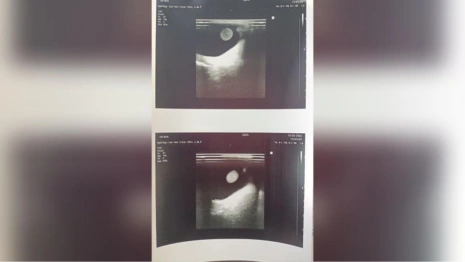

Девочка была госпитализирована в больницу с ярко выраженной слабостью, пожелтением кожных покровов, болями в области живота и значительными отклонениями биохимических показателей печени. В итоге ей поставили диагноз и отправили на лечение. Сейчас малышка чувствует себя намного лучше. Печеночные показатели уменьшились в 30 раз и пришли в норму.

Аутоиммунный гепатит – это хроническое воспаление ткани печени, возникающее вследствие атаки собственной иммунной системой клеток печени. У детей симптомы болезни развиваются медленно и часто остаются незамеченными родителями длительное время. Подтверждение диагноза требует специального анализа крови, включающего определение уровня ферментов печени (АЛТ, АСТ), общего билирубина и специфических антител против компонентов клетки печени.